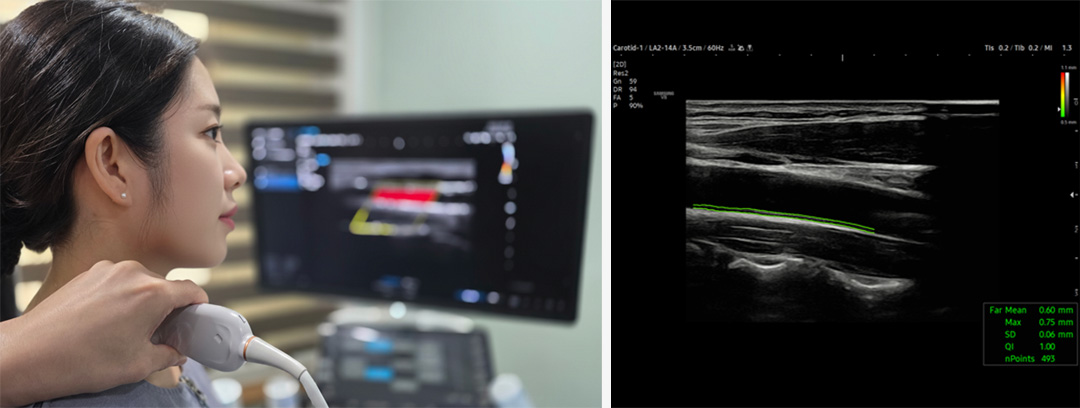

경동맥 초음파검사